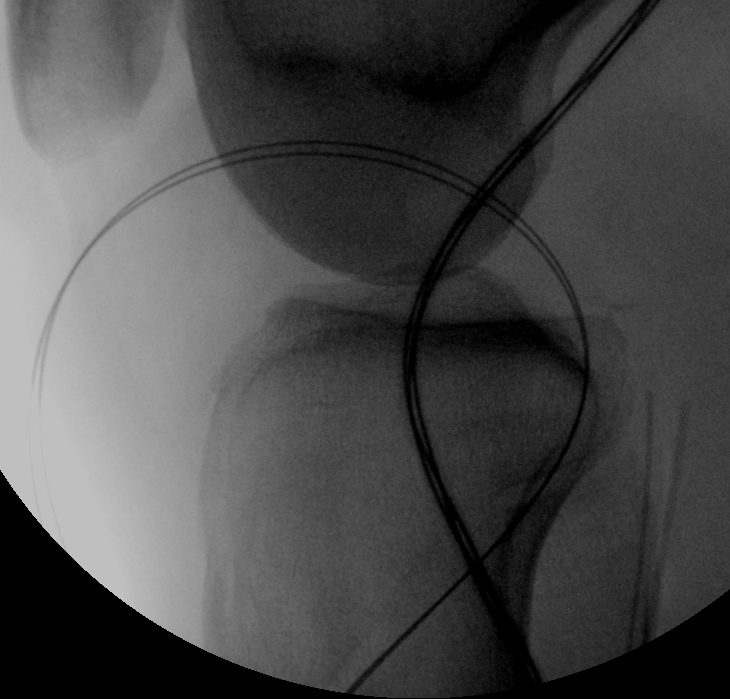

Tibial tunnel

- lateral arthroscopy portal

- small medial parapatellar approach

- insert PCL jig

- hooks over back of tibia

- check position on fluoroscopy

- pass beath pin

- drill 6 mm

- pass loop wire